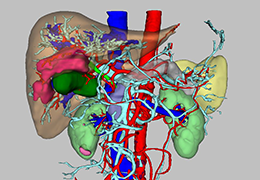

High-quality and fast 3D reconstruction and 3D rendering

Performs 3D reconstruction and volume rendering.